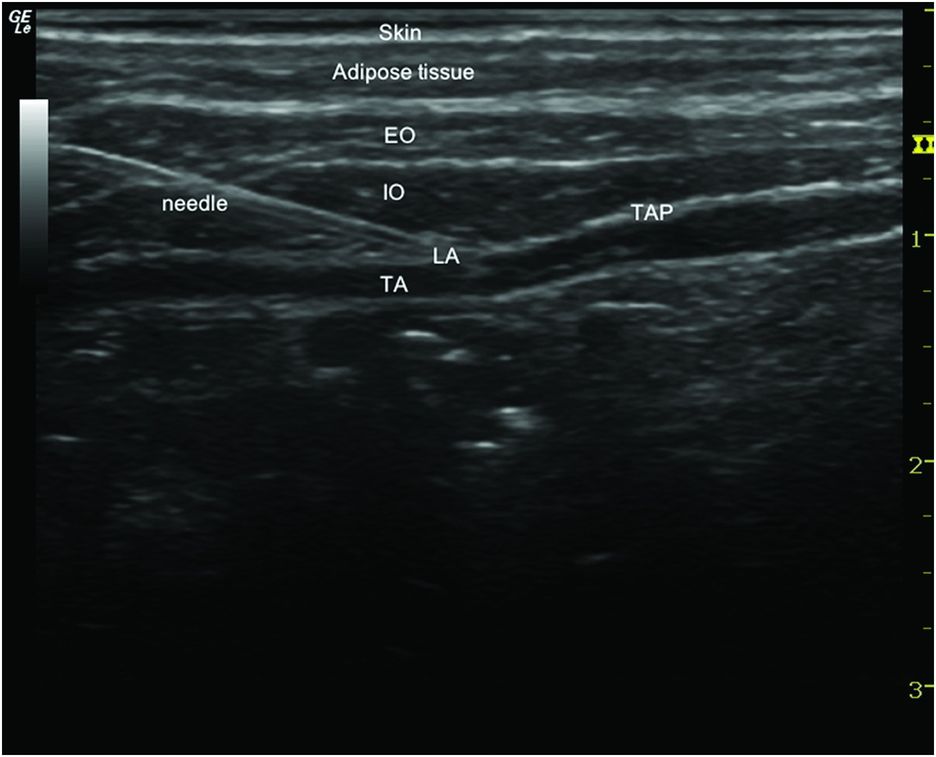

What Is Tap Block Anesthesia . Transversus abdominis plane (tap) blocks are important analgesic interventions that provide significant somatic pain relief to the abdomen. Utilizing ultrasound, transversus abdominis plane (tap) blocks can provide reliable relief of somatic incisional pain. The transversus abdominis plane (tap) block is a fascial plane block performed by injecting local anesthetic in the plane between. Transversus abdominis plane (tap) block. The transverse abdominis plane (tap) block is a peripheral nerve block designed to anesthetize the nerves supplying the anterior abdominal wall (t6 to l1). The various approaches to the tap block are differentiated by their probe placement and location of needle insertion and injection, resulting in differences in local anesthetic spread and extent. Tap blocks are a great adjunct to a multimodal. This peripheral nerve block is performed with the. Transversus abdominis plane (tap) block is a regional technique for analgesia of the anterolateral abdominal wall.

The transversus abdominis plane (tap) block is a fascial plane block performed by injecting local anesthetic in the plane between. Transversus abdominis plane (tap) block. Transversus abdominis plane (tap) blocks are important analgesic interventions that provide significant somatic pain relief to the abdomen. Utilizing ultrasound, transversus abdominis plane (tap) blocks can provide reliable relief of somatic incisional pain. Tap blocks are a great adjunct to a multimodal. The transverse abdominis plane (tap) block is a peripheral nerve block designed to anesthetize the nerves supplying the anterior abdominal wall (t6 to l1). This peripheral nerve block is performed with the. The various approaches to the tap block are differentiated by their probe placement and location of needle insertion and injection, resulting in differences in local anesthetic spread and extent. Transversus abdominis plane (tap) block is a regional technique for analgesia of the anterolateral abdominal wall.